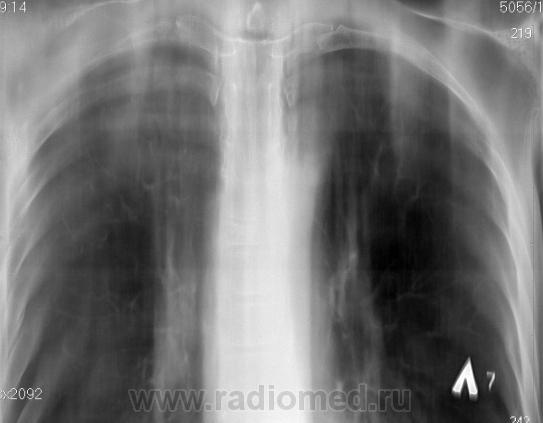

По томограммам не понятно что хотели получить? Интересовали эти маленькие плотные очаги?

Справа на верхушке инфильтративная тень. Слева в задних отделах мелкие буллы.

На последнем срезе тень в 1 сегменте, мелкие полости в верхних долях с обеих сторон.